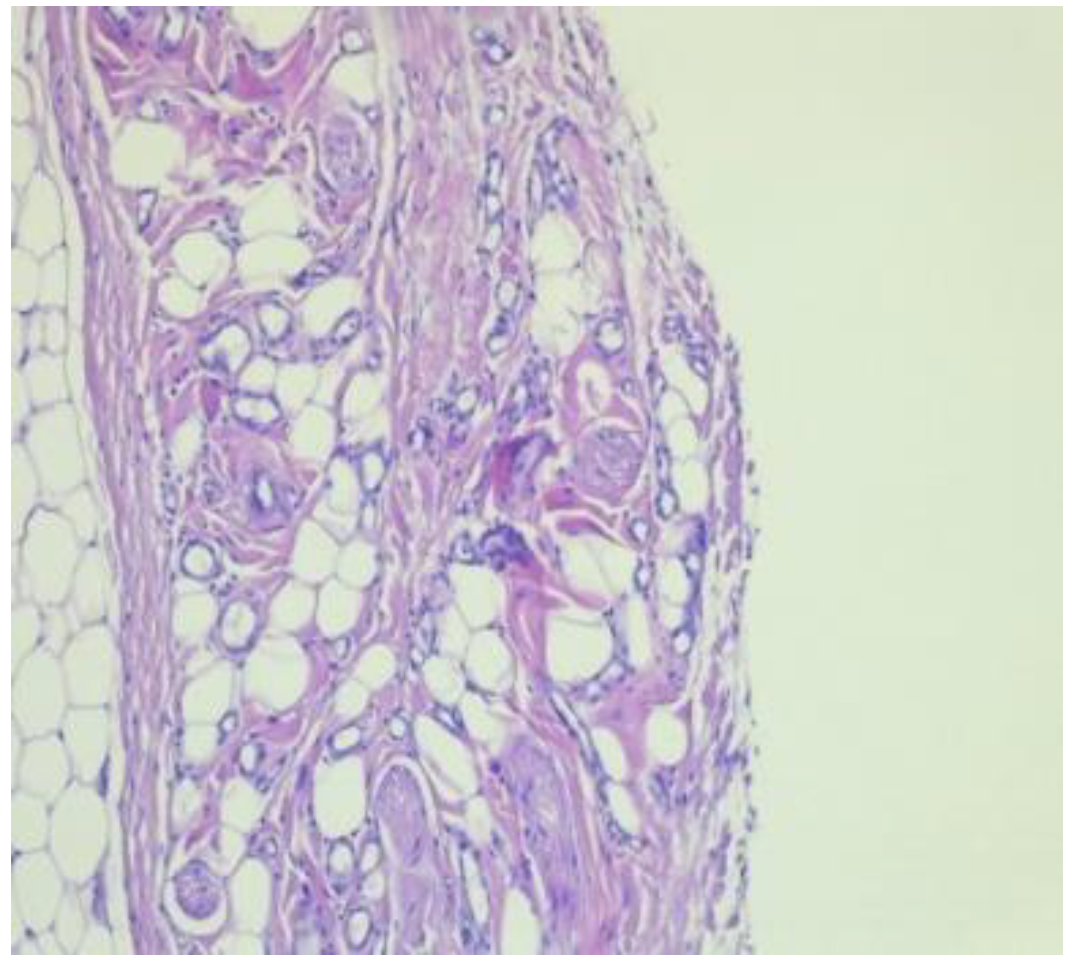

Histology assessment: in the control group was observed an active chronic inflammation associated with giant foreign body cell reaction. More specifically lymphocytes and plasma (Ly-PL) cells were associated with neutrophil Polymorphonuclear leukocytes (PMN) in 10% and giant foreign cell reaction in the proportion of 30% (Figure 5 and Figure 6).

Figure 5. High level of inflammatory infiltrate at six weeks after surgery.